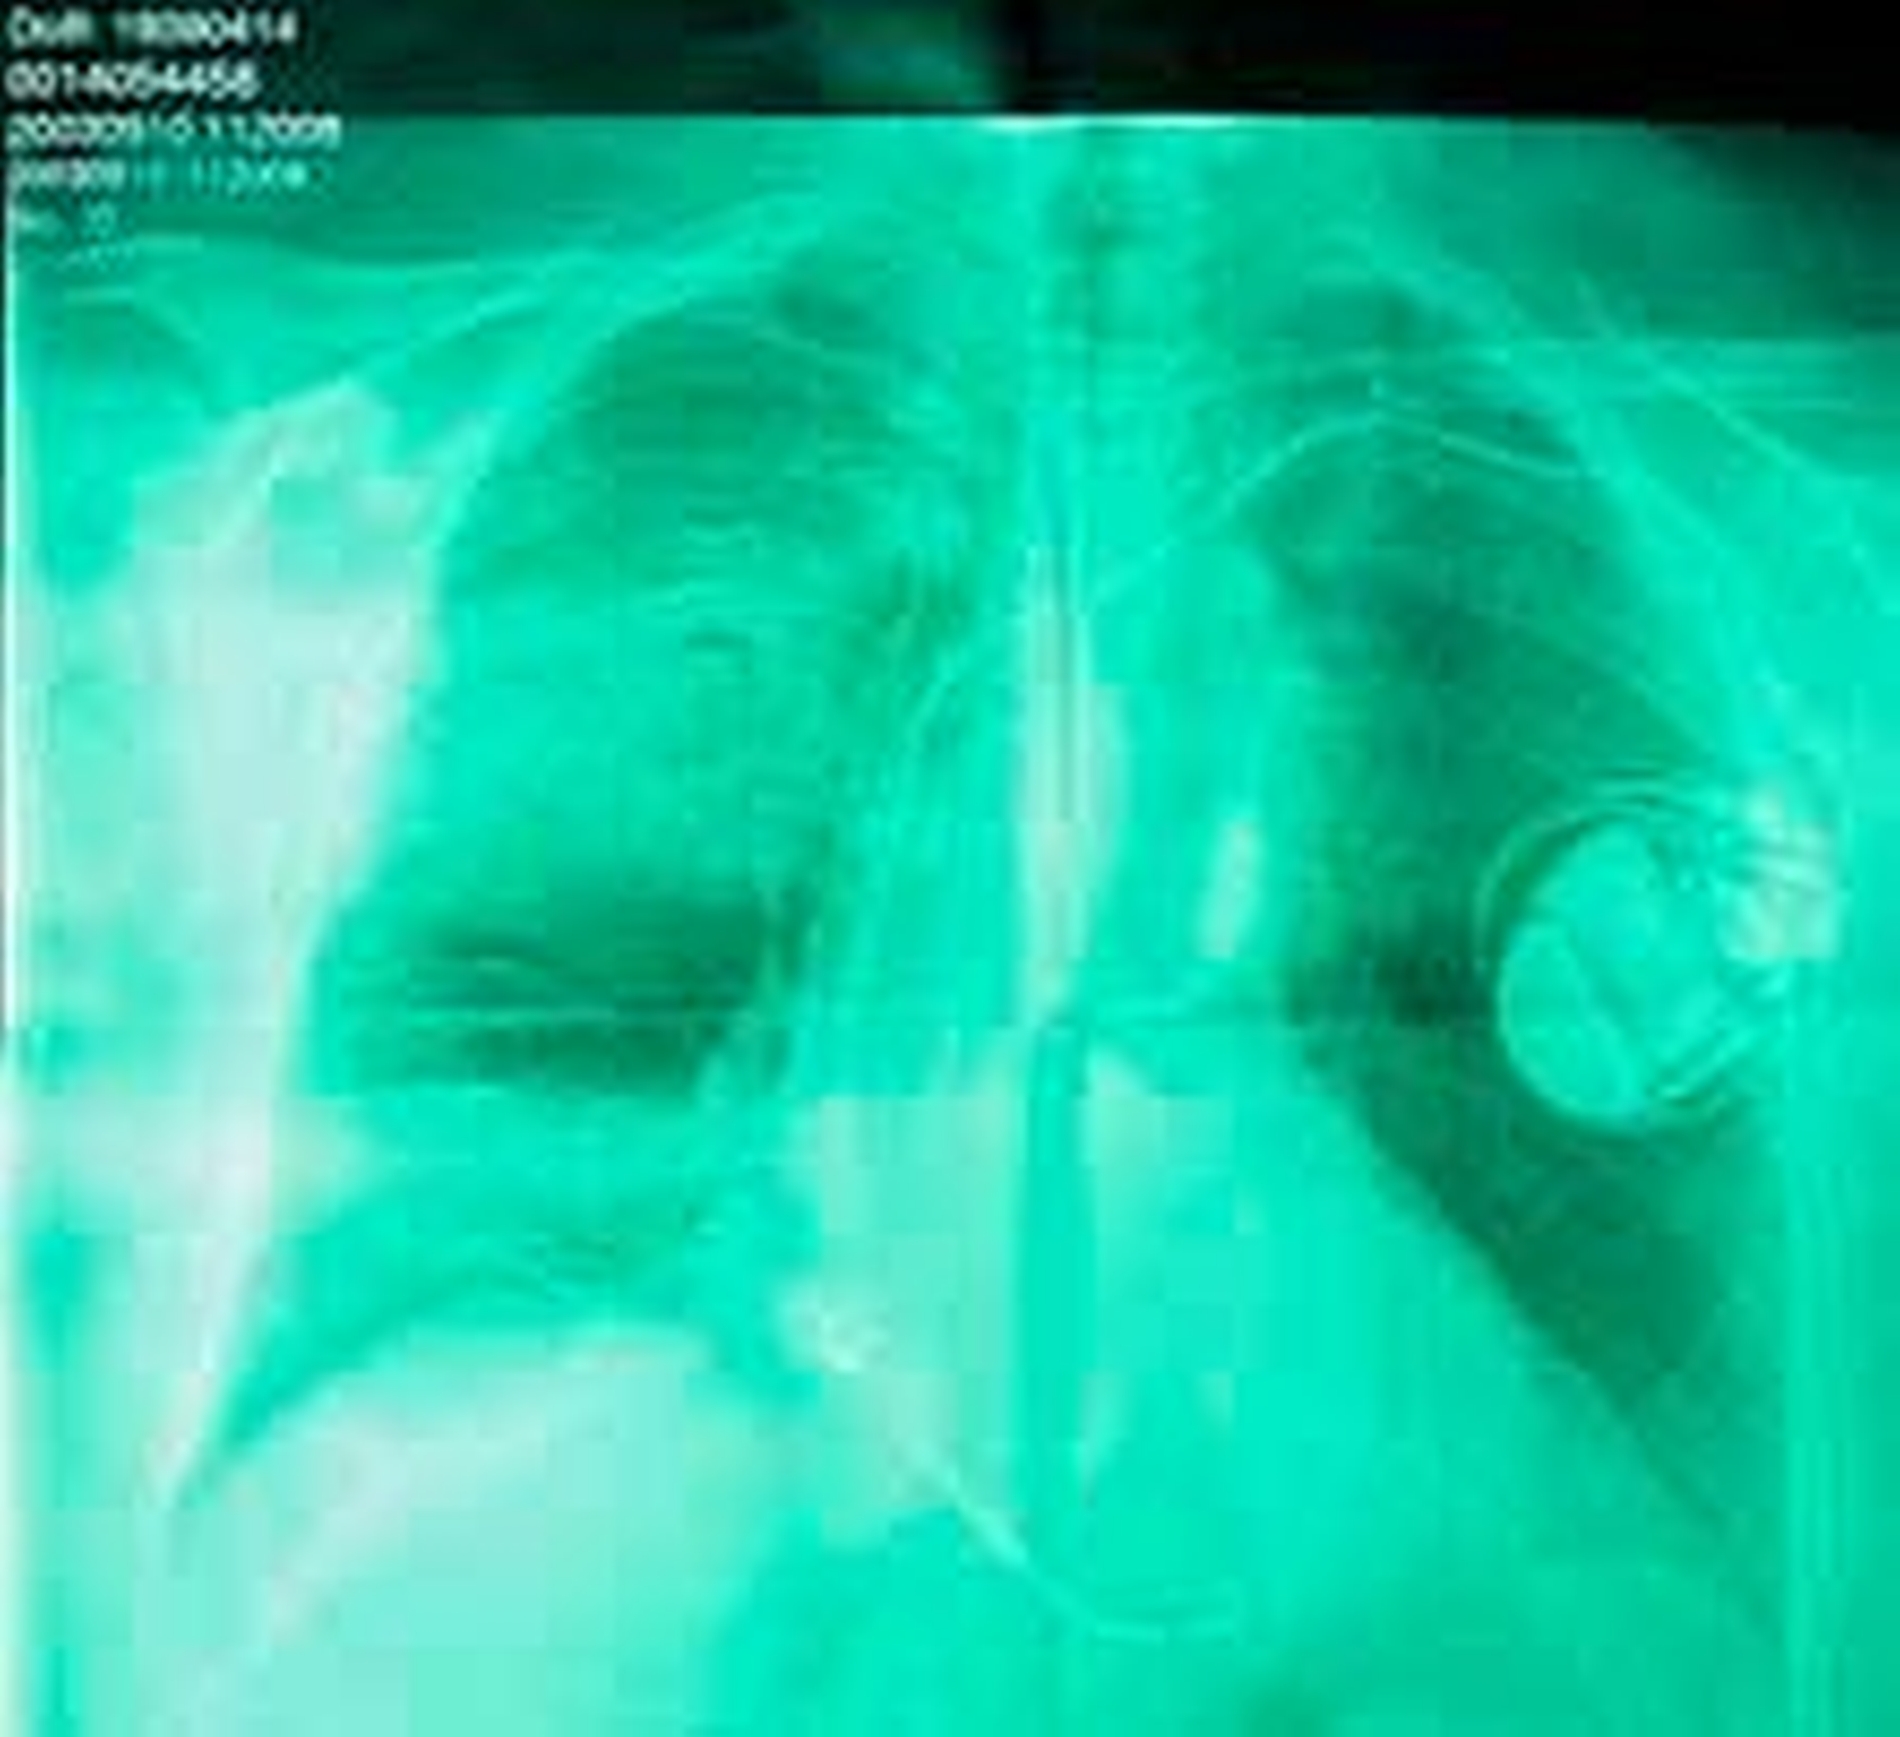

Die ante-mortem Röntgenbilder (li) der Fallbeispiele eins bis drei wurden von deutschen Zahnärztinnen und Zahnärzten zu Lebzeiten der Vermissten angefertigt. Die Bilder wurden von deutschen Kiminalisten in den Zahnarztpraxen abgeholt, die die Angehörigen der vermeintlichen Opfer bei der Aufgabe der Vermisstenanzeige benannt hatten. Die post-mortalen Röntgenbilder (re) wurden dann von den in Thailand tätigen forensischen Kolleginnen und Kollegen im Rahmen der Sektion angefertigt.

Der Vergleich beider Aufnahmen und damit die letztendliche Identifizierung erfolgte vor Ort im Auswertungszentrum durch die Zahnärzte im Einsatzgebiet.

Die ante-mortem Thorax-Aufnahme von Fall 5 wurde von Deutschland nach Thailand übermittelt. Das erfolgte nach Benennung der kardiologischen Klinik, in der der Patient in Behandlung war. Die Kardiologen haben anhand ihrer Krankenunterlagen den Hersteller des Defibrillators, das Modell und die Seriennummer benannt und bekannt gegeben. Diese Daten wurden dann in Thailand mit den nach der Obduktion bekannten Angaben verglichen. Die Übereinstimmung der Daten führte schließlich zur Identifizierung.